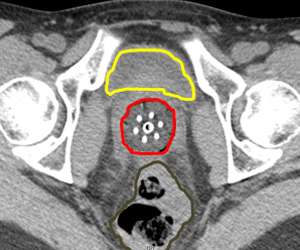

An alternative to this is to use CT compatible applicators and to use CT imaging. The advantage of this is that CT imaging allows you to see the anatomy in more detail than on X-rays. For example, a CT image with a vaginal applicator in place looks like the following:

CT Scan

One can actually "see" the anatomy including the bladder (yellow) and rectum (brown). The cylinder is outlined in red. By being able to clearly see things we can more effectively optimize the radiation dose to the target and limit the dose to normal tissues.